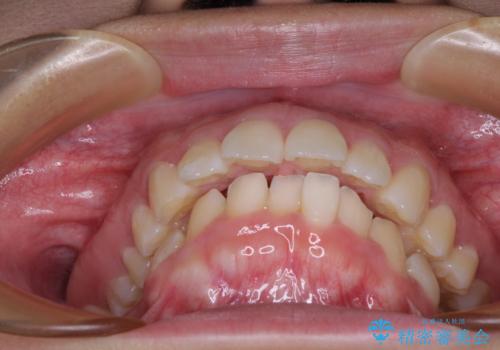

- 上顎前歯が飛び出していて唇がうまく閉じられないとのことで来院された患者様です。

くちばしのように前歯が突出していたため、口元を積極的に引っ込めるために、上下左右の小臼歯4本を抜歯することとしました。

上下正中位置を改善するため、左下はイレギュラーに第二小臼歯を抜歯しました。そのため治療期間の長期化が予想されましたが、2年半ほどで期待通りの歯列に仕上げることができました。